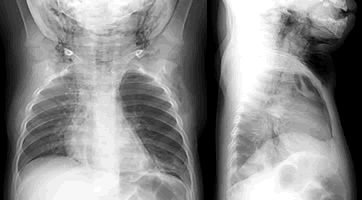

診斷:對嚴重胸部鈍性創傷的病人,來急診時即有嚴重呼吸困難和發紺,查體發現張力性氣胸、氣胸、縱隔氣腫和下頸部氣腫有重要意義,即使無氣胸也是X 線胸像上提示氣管破裂的最敏感的徵象。最可靠的診斷氣管破裂的方法是纖維支氣管鏡檢查。所有臨床上懷疑有氣管損傷的病人,如情況允許,均應立即行纖維支氣管鏡檢查來確立診斷,以防延誤診斷造成死亡或並發其他問題。張力性氣胸和氣胸安置胸腔閉式引流後,發現大量氣體持續外漏,隨吸氣動作而加重,根據上述體徵也可確診,病情平穩後,立即做X 線胸片證實診斷。對大多數無並發大咯血的病例,不必急於做支氣鏡檢或其他檢查。其他輔助檢查:

胸CT2.氣管CT 斷層檢查 可發現氣管斷裂的直接徵象,氣管透亮帶的變形及不連續,甚至有錯位的徵象。